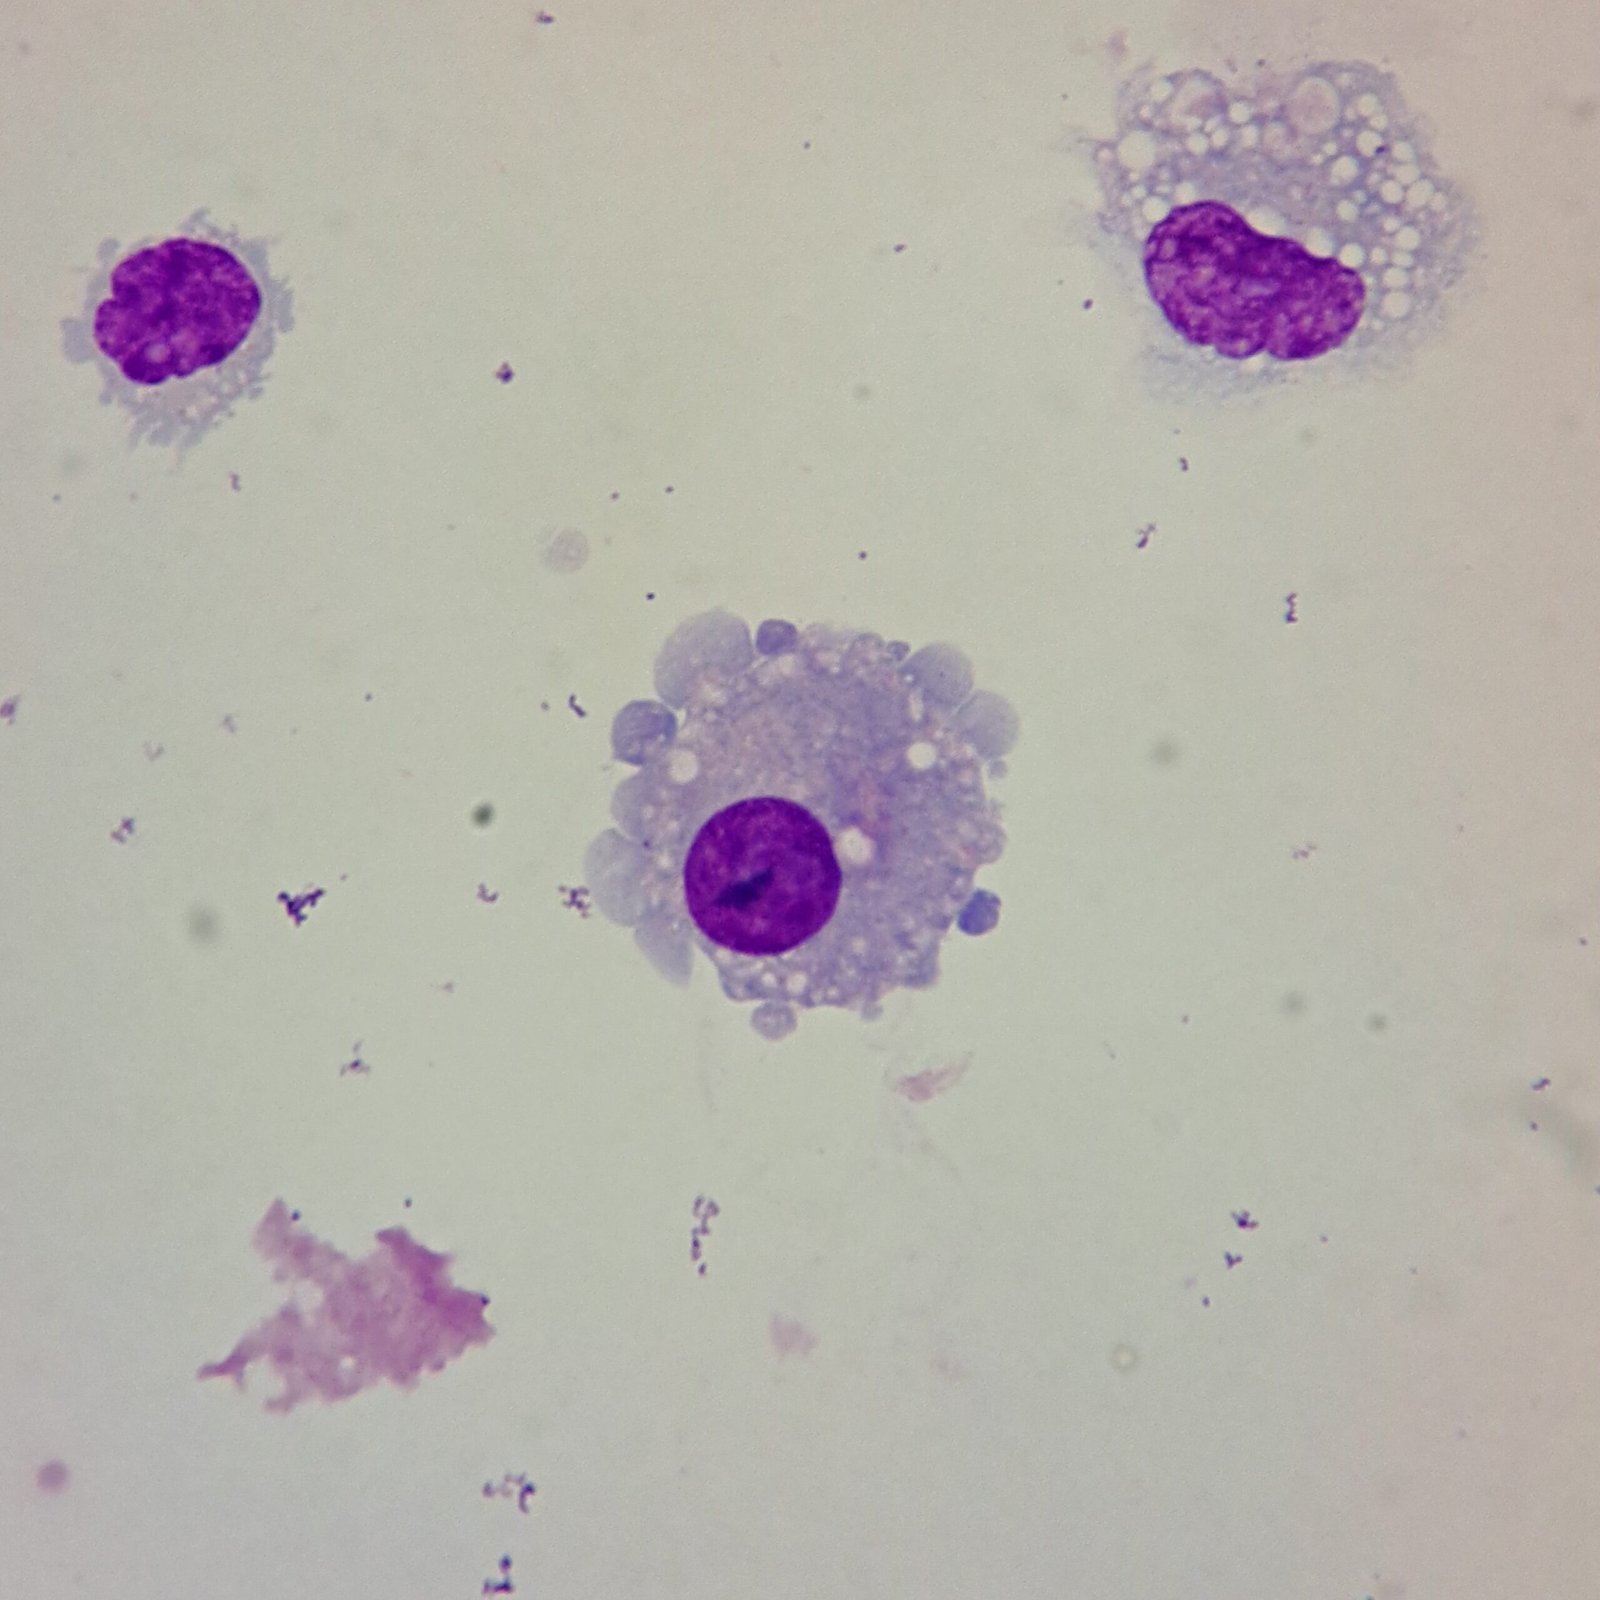

Mesothelial cells are described as having a “fried egg” appearance. They have a round to oval nucleus with smooth borders and evenly distributed chromatin. Nucleloli are usually present. Mesothelial cells may also be multinucleated.

Cells may be seen in clumps, but “windows” between cells still allows for individual counting.

Macrophages are about the same size as mesothelial cells, so the two can often be confused. Macrophages can usually be differentiated by the presence of vacuoles and a lacey chromatin. If both cell types are present and differentiation is difficult, take a look around the slide to get an idea of each kind of morphology before starting a differential.